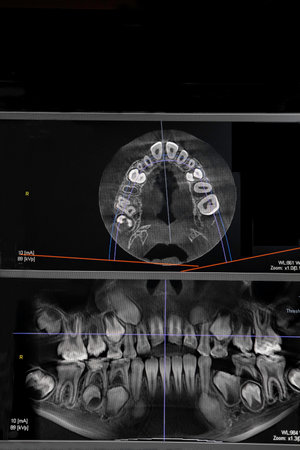

The male hand of the dentist on the monitor screen shows the jaw.

The male hand of the dentist on the monitor screen shows the jaw.

CT image of the teeth of a 9-year-old child, with baby teeth, in different projections. CBCT of two jaws.